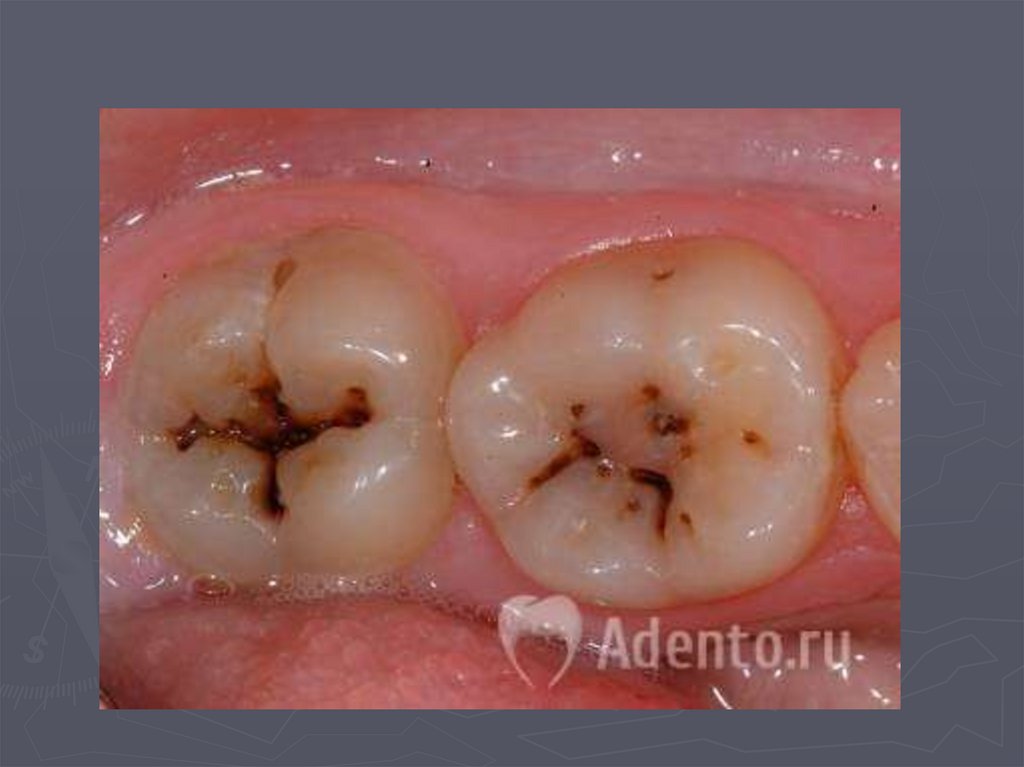

37. КЛИНИЧЕСКАЯ КАРТИНА СРЕДНЕГО КАРИЕСА при компенсированной форме:

► отмечается быстропроходящая боль от

химических, термических, иногда от

механических, раздражителей;

► края кариозной полости закругленные, ровные;

► эмаль плотная;

► дентин плотный, пигментированный;

► при зондировании болезненность определяется

по эмалево-дентинному соединению.

38. КЛИНИЧЕСКАЯ КАРТИНА СРЕДНЕГО КАРИЕСА при декомпенсированной форме:

► при локализации кариозной полости в фиссурах

определяется небольшое входное отверстие;

► при раскрытии обнаруживается кариозная

полость с податливым дентином;

► края кариозной полости нависают;

► эмаль тонкая, хрупкая;

► дентин светлый, влажный, размягченный, легко

удаляется экскаватором;

► зондирование болезненно по

эмалево-дентинному соединению.